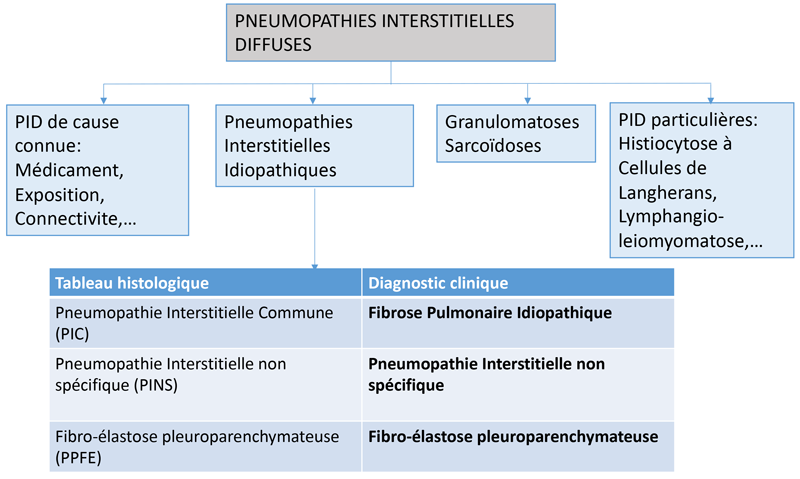

Le diagnostic et la prise en charge des PID repose sur une classification faisant porter un poids important à l’étiologie de la PID (Figure 1) (connectivite, exposition professionnelle, environnementale, …) et le diagnostic de la PID s’arrêtait jusqu’à récemment à ce point. Les découvertes génétiques récentes et les progrès thérapeutiques montrent qu’il existe un continuum entre les PID secondaires et idiopathiques et qu’il faut probablement prendre en compte d’autres données comme le caractère progressif de la PID pour classer et traiter de manière personnalisée les patients atteints de PID.

Figure 1 Classification actuelle des pneumopathies interstitielles diffuses (PID) séparant les PID secondaires des PID idiopathiques.